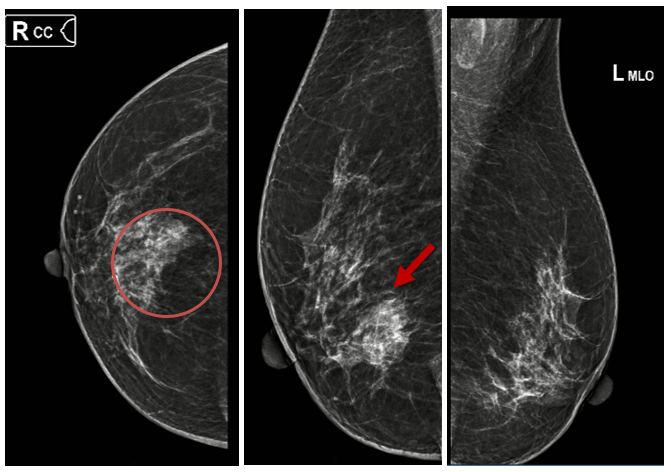

X-quang tuyến vú: Hình ảnh đám tăng đậm độ kèm vi vôi hóa vú góc 1/4 dưới ngoài vú phải: đám tăng đậm độ bờ không rõ kích thước khoảng 25x18mm, bên trong có vài nốt vi vôi hóa tạo cụm, đường kính vôi hóa 0.3mm (Phân loại BIRADS 4). Phối hợp siêu âm có khối giảm âm vú phải (Phân loại BIRADS 4c).

Hình 1. Hình ảnh X-quang tuyến vú: đám tăng đậm độ kèm vi vôi hóa vú góc 1/4 dưới ngoài vú phải (vòng tròn đỏ và mũi tên đỏ).